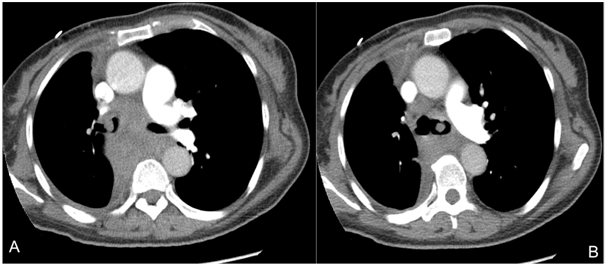

A 53-year-old woman presented to the emergency department with massive hemoptysis and respiratory failure. She had had history of intermittent hemoptysis and worsening shortness of breath during the last year. Her past medical history was remarkable for recently diagnosed lung cancer, two months previous to the admission. A metastatic poorly differentiated lung adenocarcinoma was reported in pathology from another medical center. On admission she required or tracheal intubation. The physical examination was, otherwise, unremarkable. She was hemodynamically stable and did not require vasopressor. Platelets and coagulation studies were in the normal range. A chest CT-scan with contrast showed evidence of a 6-cm-diameter right perihilar tumor, with extension to bilateral main-bronchi (Figure 1). There was secondary 70% left-main-bronchi obstruction and right-main-bronchi almost obliteration. Endobronchial obstruction due to advanced lung cancer was considered. A therapeutic bronchoscopy was performed. It showed 90% obstruction of bilateral main-bronchi by easily bleeding polypoid mass. Resection by cauterization was performed, allowing bleeding control and permeabilization of the airway. Samples were sent to pathology.

Figure 1 A, B. Chest CT-Scan showing bilateral endobronchial obstruction secondary to an infiltrative parahiliar right mass involving the carina and extending to bilateral main-bronchi.